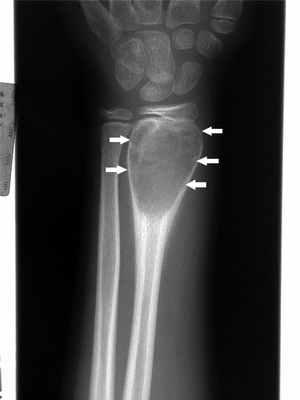

Неоссифицирующая фиброма (фиброзный кортикальный дефект, фиброксантома)

Неоссифицирующая фиброма представляет собой доброкачественное фиброзное поражение кости, которое на рентгенограмме выглядит как четко очерченное светлое кортикальное поражение. Очень маленькую неоссифицирующую фиброму обозначают как фиброзный кортикальный дефект. Эти изменения представляют собой дефекты развития, в которых часть кости, подвергающаяся в норме оссификации, заполняется фиброзной тканью. Обычно они возникают в области метафизов, особенно часто в дистальном отделе бедра, в дистальном и проксимальном отделах большеберцовой кости. Они могут прогрессивно увеличиваться и становиться мультиочаговыми. Неоссифицирующие фибромы часто встречаются у детей. Большинство поражений в конечном итоге оссифицируются и подвергаются ремоделированию, что в большинстве случаев приводит к образованию плотных склеротических участков. Тем не менее, некоторые дефекты увеличиваются.

Небольшие неоссифицирующие фибромы протекают бессимптомно. Однако, при вовлечении около 50% диаметра кости появляются боли и увеличивается риск патологических переломов.

Неоссифицирующие фибромы обычно выявляют случайно при инструментальном исследовании (например, после травмы). Зачастую они выглядят как одиночные продолговатые зоны просветления менее 2 см в диаметре, с четким склеротическим ободком в кортикальном слое. Они также могут быть многоочаговыми.

Маленькие неоссифицирующие фибромы не требуют лечения, но больной должен находиться под наблюдением. Дефекты, которые вызывают боль и составляют 50% от диаметра кости, являются показанием к удалению и трансплантации кости, что позволяет снизить риск патологического перелома.

- Неоссифицирующая фиброма (фиброзный кортикальный дефект)

Неоссифицирующая фиброма (фиброзный кортикальный дефект, фиброксантома) представляет собой доброкачественный фиброзный дефект кости, который на рентгенограмме выглядит как четко очерченная зона повышенной прозрачности. Очень маленькую неоссифицирующую фиброму обозначают как фиброзный кортикальный дефект. Эти изменения представляют собой дефекты развития, в которых часть кости, подвергающаяся в норме оссификации, заполняется фиброзной тканью. Обычно они возникают в области метафизов, особенно часто в дистальном отделе бедра, в дистальном и проксимальном отделах большеберцовой кости. Неоссифицирующие фибромы часто встречаются у детей. В большинстве случаев изменения в итоге оссифицируются и подвергаются ремоделированию, часто с формированием плотных склеротических зон. Тем не менее, некоторые дефекты увеличиваются. Часто являются случайными находками при рентгенологическом исследовании.

Опасность: патологический перелом при прогрессирующем росте. В этом случае показано хирургическое лечение.